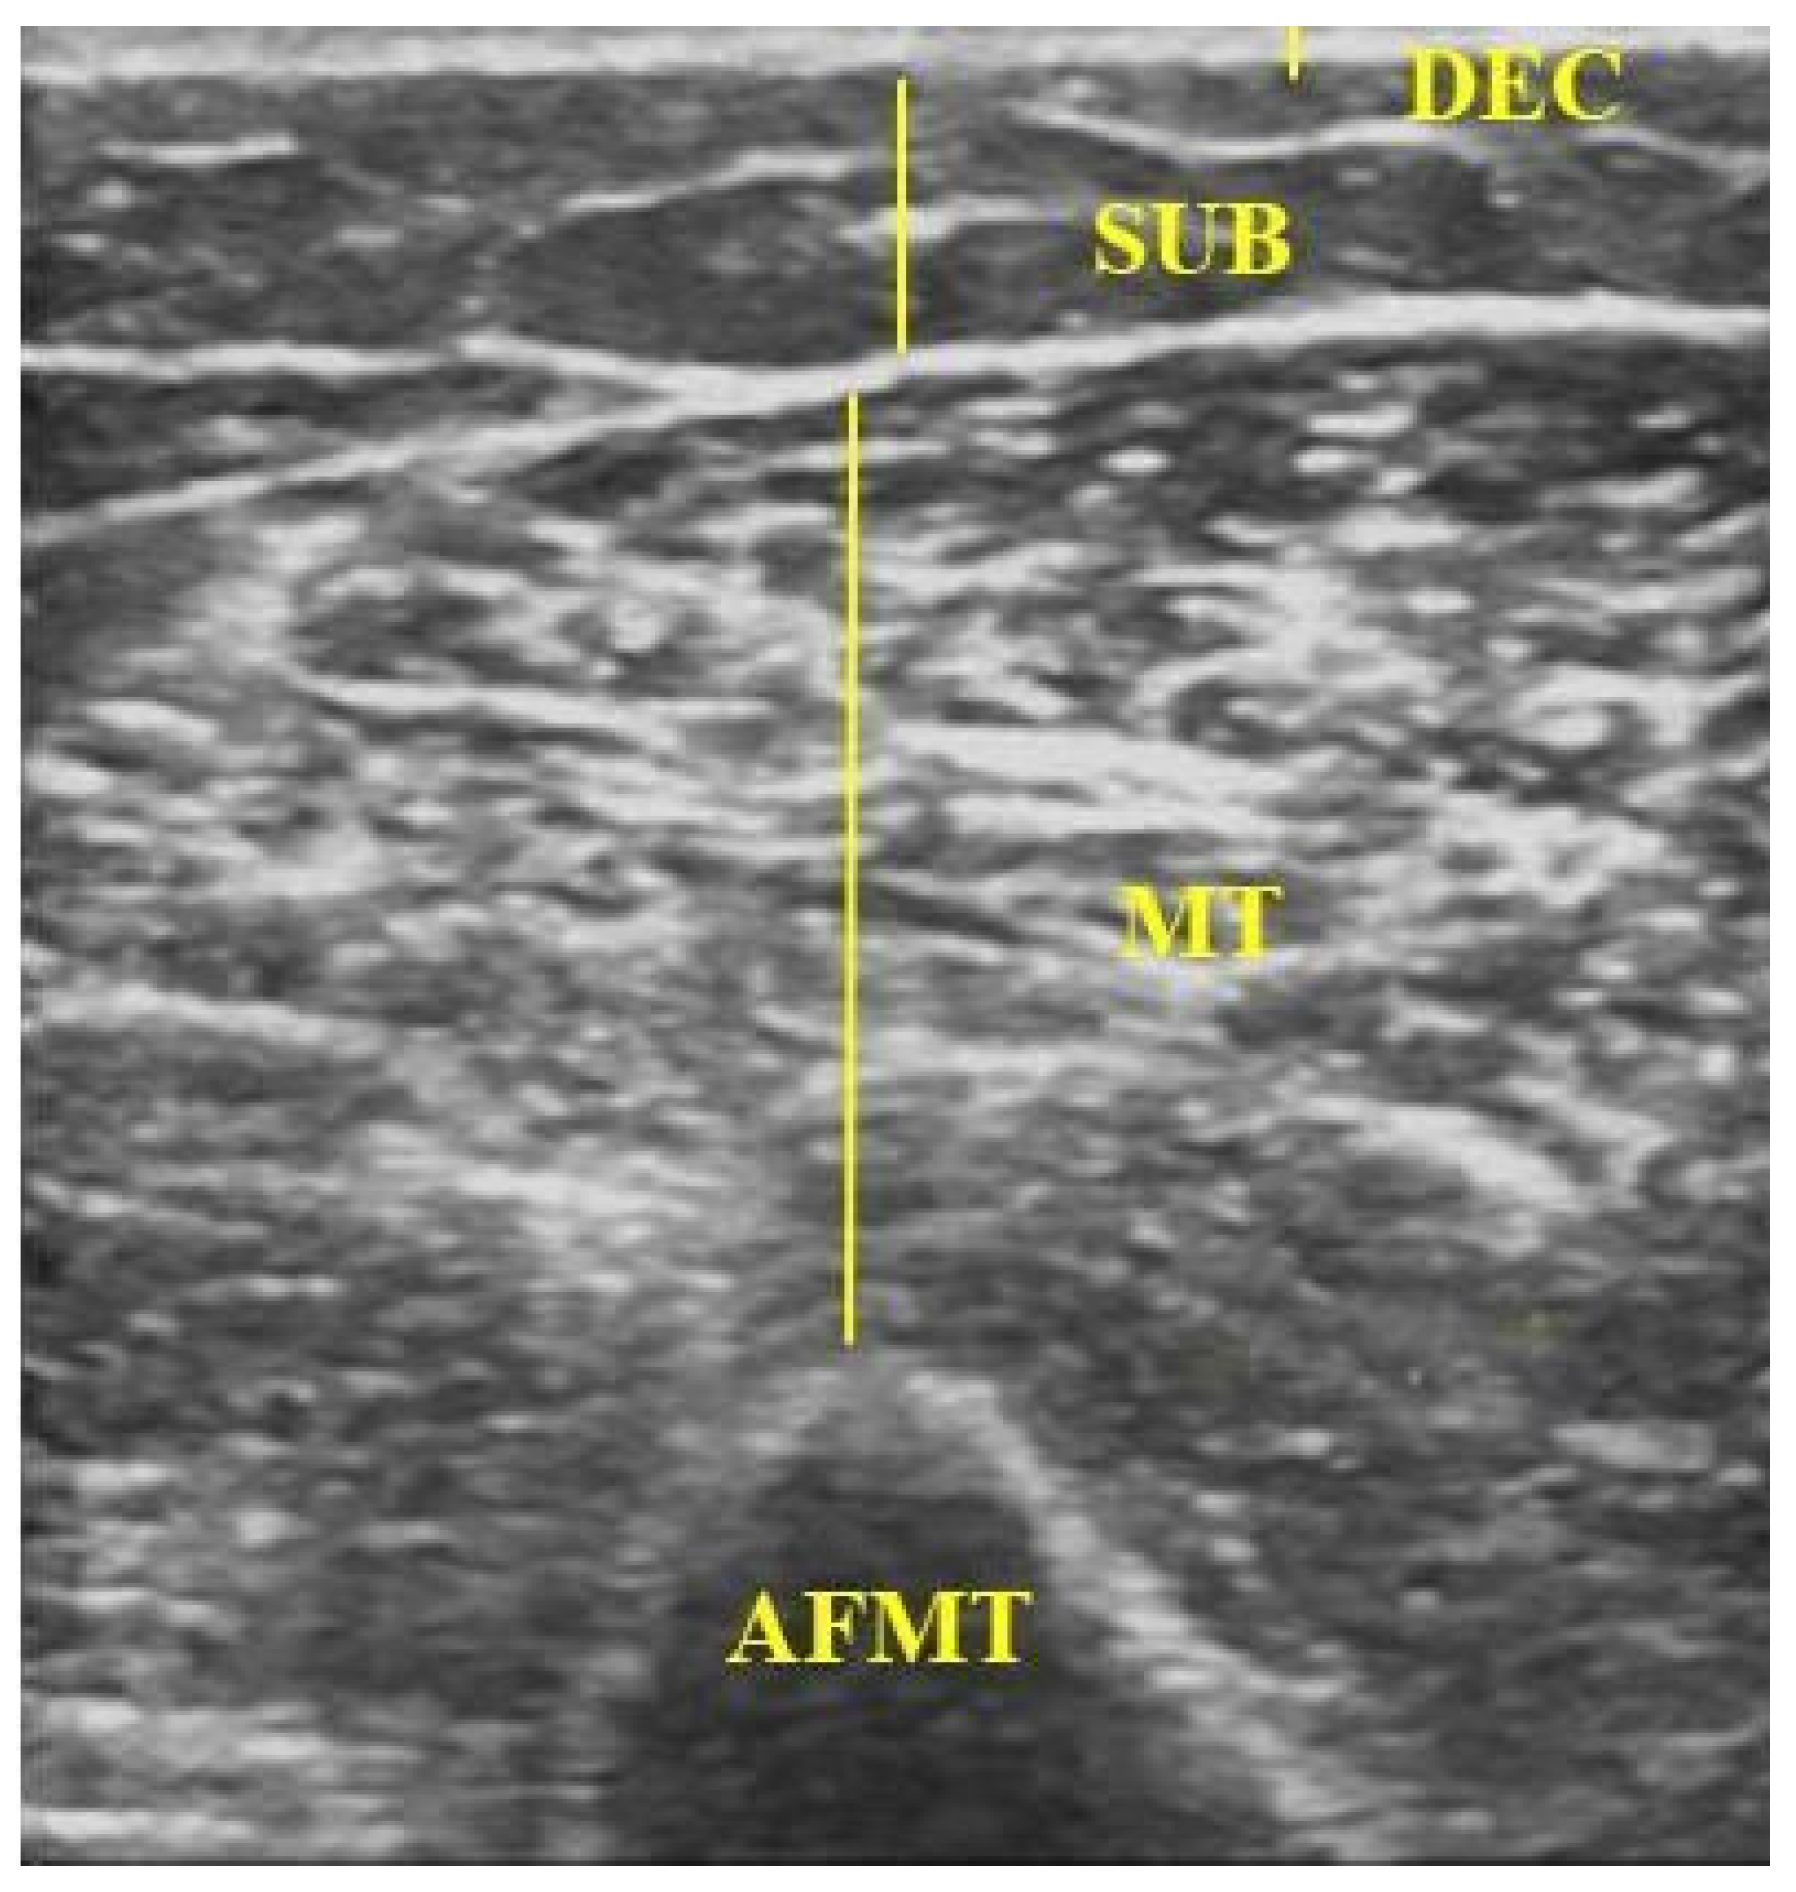

| DEC | dermal–epidermal complex |

| SUB | subcutaneous tissue |

| MT | muscle thickness |

| AFMT | arm flexor muscle thickness |